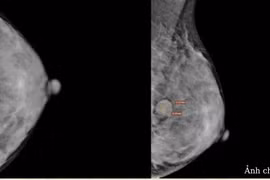

Ung thư vú là loại ung thư thường gặp gây tử vong nhiều nhất ở phụ nữ sau 35 tuổi. Phát hiện sớm ung thư vú rất quan trọng, giúp điều trị bệnh hiệu quả hơn.

Bị bong tróc nhũ hoa, ngứa, tưởng bệnh viêm da và dấu hiệu tiền mãn kinh, người phụ nữ đi khám phát hiện bệnh ung thư vú ít gặp, may mắn đang ở giai đoạn 0.

Ung thư vú là nguyên nhân gây tử vong hàng đầu trong các loại ung thư ở phụ nữ trên thế giới. Tuy nhiên, có một số nhóm người có nguy cơ cao mắc ung thư vú.